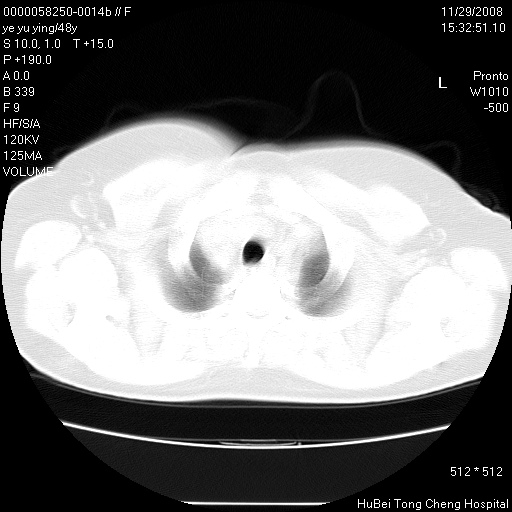

以下是引用zsl6918在2008-11-29 21:47:00的发言:[br]恶性肿瘤病史,转移瘤首先考虑。脂肪肝,胆囊结石。

以下是引用huenhao在2008-11-29 22:11:00的发言:[br]脂肪肝,胆囊结石。左肺病灶建议定期复查。

以下是引用liuyue在2008-11-30 5:44:00的发言:[br]1.左肺病变,首先考虑感染性病变,转移待排;建议治疗后复查。[br]2.肝脏密度普遍减低,考虑与化疗有关。[br]3.胆囊结石.